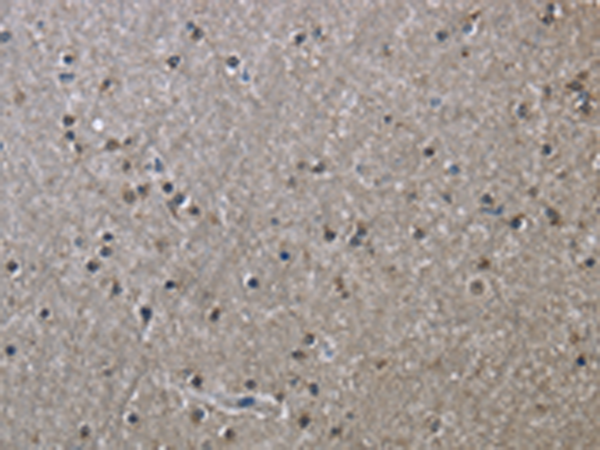

分类: 科研抗体货号: P01378别名: SLIM2应用: WB,IHC反应种属: Human, Mouse

分类: 科研抗体货号: P01441别名: RNMX; HNRPG; HNRNPG; RBMXP1; RBMXRT; hnRNP-G应用: WB,IHC反应种属: Human, Mouse, Rat

分类: 科研抗体货号: P01373别名: FHFR; FGFR5应用: WB,IHC反应种属: Human, Mouse, Rat

分类: 科研抗体货号: P01433别名: HL; HTGL; LIPH; HDLCQ12应用: WB,IHC反应种属: Human, Mouse

分类: 科研抗体货号: P01458别名: CBAS1; PFIC4; SDR11E3应用: IHC反应种属: Human, Mouse, Rat

分类: 科研抗体货号: P01432别名: HCCR; HCCR1; HCCR2; HCCR-1; HCCR-2; HCRR-2; SLC55A3; 1110019O13Rik应用: WB,IHC反应种属: Human, Mouse

分类: 科研抗体货号: P01454别名: HSE; RODH; SDR9C6应用: WB,IHC反应种属: Human, Mouse

分类: 科研抗体货号: P01426别名: CSA; MOT; MOT2; GRP75; PBP74; GRP-75; HSPA9B; MTHSP75; HEL-S-124m应用: WB,IHC反应种属: Human, Mouse, Rat

分类: 科研抗体货号: P01425别名: GPRK5; FP2025应用: IHC反应种属: Human, Mouse, Rat